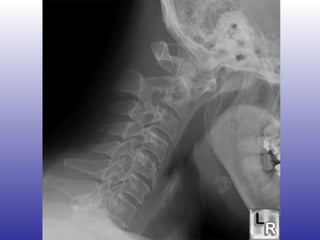

Compromiso cervical Prevalencia: 4-60% FR: Inicio en edades avanzadas Sinovitis muy activa Compromiso erosivo periférico rápidamente progresivo Puede comprometer art. Atlantoaxial y subaxiales (entre C1-C2) Subluxación anterior, posterior o vertical

Compromiso cervical Síntomas subluxación: Cefalea occipital Cuadraparesia espástica Analgesia en manos o pies Episodios autolimitados de disfunción medular Al mover las manos, parestesias en brazos u hombros

Compromiso cervical Signos subluxación: Pérdida lordosis occipitocervical Resistencia a movilidad pasiva Protrusión anormal del arco axial Episodios autolimitados de disfunción medular Signos neurológicos: Reflejos osteotendíneos aumentados Babinsky (+) Debilidad, espasticidad o atrofia muscular

Imagenología Rx cervical lateral  ¿Cuello en flexión? > 3 mm de separación entre el diente del odontoides y el arco anterior del axis Línea espinolaminar hacia posterior en C2

Compromiso cervical Prevalencia:4-60% FR: Inicio en edades avanzadas Sinovitis muy activa Compromiso erosivo periférico rápidamente progresivo Puede comprometer art. Atlantoaxial y subaxiales (entre C1-C2) Subluxación anterior, posterior o vertical

Compromiso cervical Síntomassubluxación: Cefalea occipital Cuadraparesia espástica Analgesia en manos o pies Episodios autolimitados de disfunción medular Al mover las manos, parestesias en brazos u hombros

Compromiso cervical Signossubluxación: Pérdida lordosis occipitocervical Resistencia a movilidad pasiva Protrusión anormal del arco axial Episodios autolimitados de disfunción medular Signos neurológicos: Reflejos osteotendíneos aumentados Babinsky (+) Debilidad, espasticidad o atrofia muscular

Imagenología Rx cervicallateral ¿Cuello en flexión? > 3 mm de separación entre el diente del odontoides y el arco anterior del axis Línea espinolaminar hacia posterior en C2